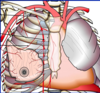

What is a coronary bypass graft?

A procedure to bypass a blocked section of a coronary artery and to deliver oxygen to the heart